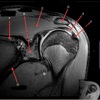

1

Q

What is letter A?

A

SUPRASPINATUS TENDON

What is letter B?

ACROMION

3

CORACOID PROCESS

4

DELTOID MUSCLE

5

What is letter C?

INFRASPINATUS MUSCLE

6

What is letter D?

SUPRASPINATUS MUSCLE

7

SUBSCAPULARIS MUSCLE

8

HEAD OF HUMERUS

9

10

GLENOID

11

ANTERIOR LABRUM

12

BICEPS TENDON (LONG HEAD)

15

TERES MINIR MUSCLE

16

17

18